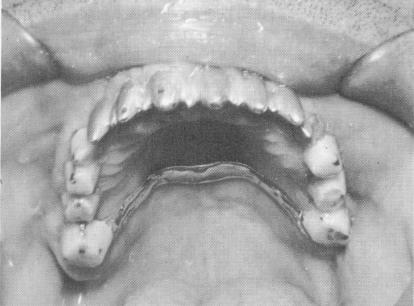

Fig. 10-237. Acrylic cores were built up to secure the pins and then prepared for full crown restorations.

Fig. 10-238. A full arch rubber base impression was then taken.